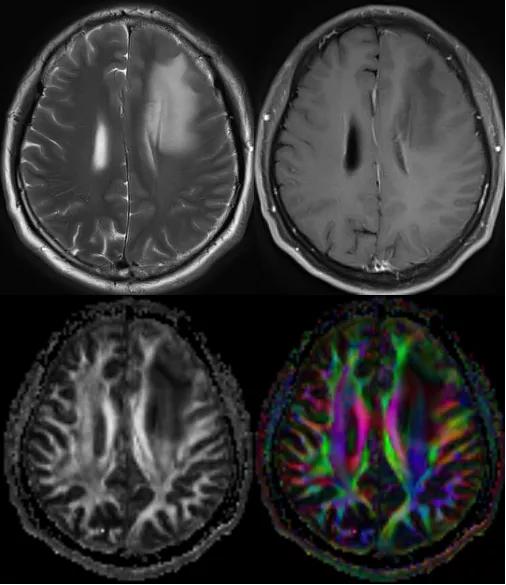

(2)肌萎缩侧索硬化

肌萎缩侧索硬化(Amyotrophic Lateral Sclerosis,ALS):ALS是一类进行性肌肉无力,伴有球麻痹症状的疾病,通常在发病后6年内死亡,T2WI可在内囊后肢、大脑脚等皮质脊髓束走行区发现异常高信号。DTI则对皮质脊髓束变性的范围和严重程度有很大帮助,并利于早期发现病变,在T2WI信号变化之前即可获得ADC的升高和FA的降低,这些微小的变化反映了继发轴索脱失后细胞外容积的扩大。